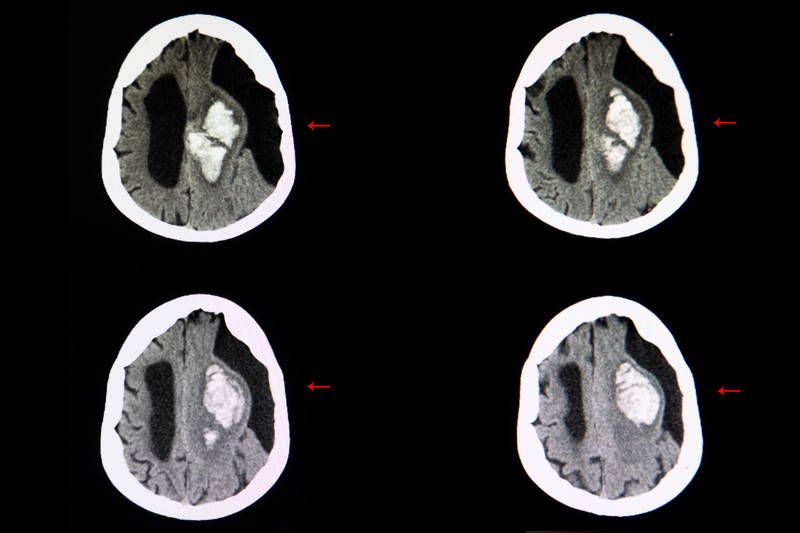

A subarachnoideális ciszta agy-gerincvelői folyadékkal telt hólyag, ami kialakulhat az agy és a koponyaalap között, vagy az arachnoideális hártyán. A legtöbb eset a gyermekkorban alakul ki, habár néha a felnőttkorban is előfordulhat. Arachnoideális ciszták férfiakban gyakrabban fordulnak elő.